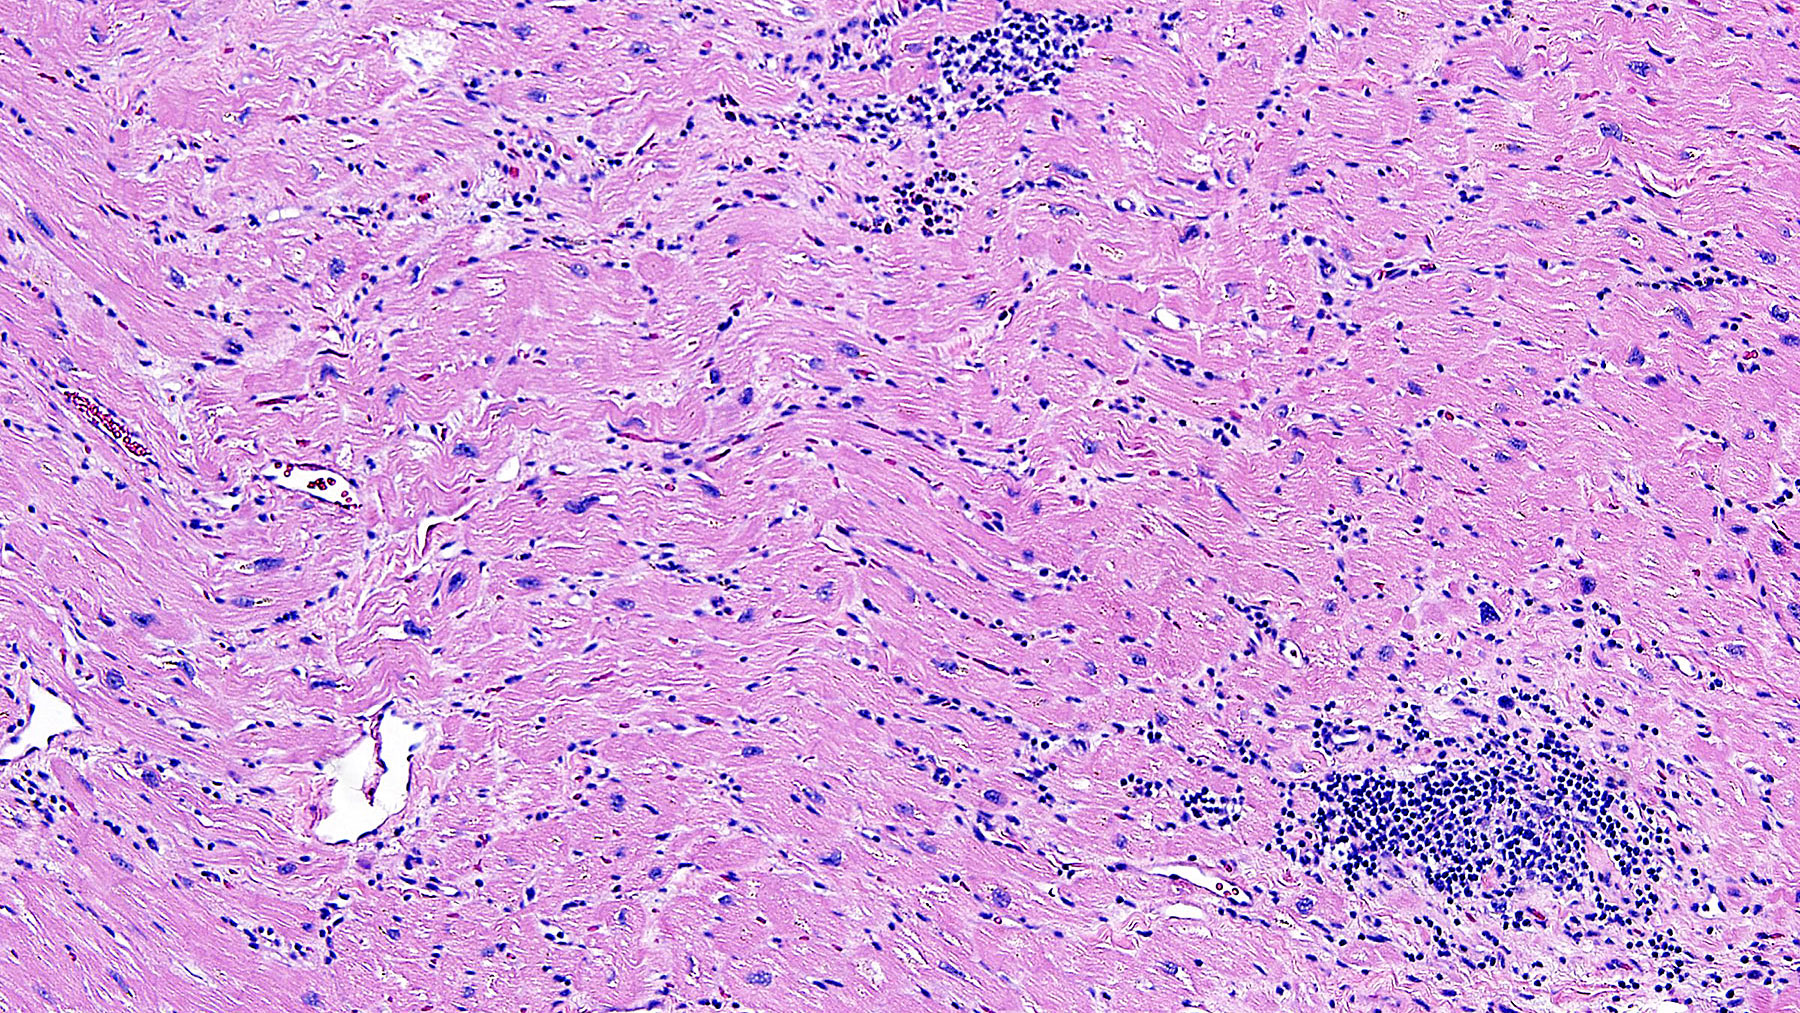

Figure A: H&E staining (10x)

Histology: H&E stains ( Figures A, B, C, and D) show Chronic interstitial myocarditis with mild to moderate infiltration of interstitial spaces with mononuclear cells admixed with scattered eosinophils and diffuse fibrosis.